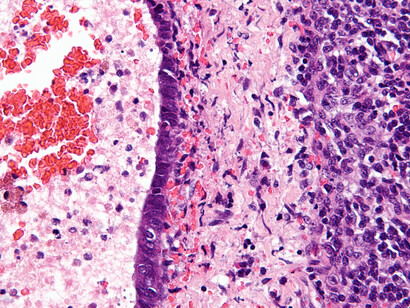

Endometriosis

Se produce cuando el revestimiento del útero (el endometrio) es muy rebelde y decide crecer en lugares donde no debería, como en los ovarios, las trompas de Falopio e incluso en otros órganos. Al llegar la regla, estos tejidos "rebeldes" también sangran y causan dolor, inflamación y, en algunos casos, la formación de tejido cicatricial (llamado tejido fibroso o adherencias).

Pruebas para detectar la endometriosis

Es muy probable que tu gine te haga un cuestionario previo. Lógicamente, si la sospecha es alta, te prescribirá pruebas diagnósticas para detectarla. Las más habituales son una ecografía, una biopsia, una resonancia magnética, un análisis de sangre y un examen pélvico. ¡Tranquila, no te va a hacer todas, el "médicx" sabe cuáles son las indicadas para ti!

A lo mejor te asustas si te piden hacer una biopsia de endometrio, pero no te preocupes, es un procedimiento rápido y el dolor es bastante leve, parecido al de la menstruación. A veces, te pueden sugerir tomar un analgésico antes de la prueba.

En cuanto a la ecografía, otra prueba común para detectar la endometriosis puede realizarse a través de la pelvis o la vagina. Es recomendable ir al baño antes para facilitar una mejor visión a través de la ecografía vaginal.

La endometriosis es una afección seria y el diagnóstico temprano es clave para abordarla de manera efectiva. El problema es que, en muchos casos, el dolor menstrual se normaliza tanto que puedes pasar años sin un diagnóstico adecuado y sin saber por qué estás sufriendo tanto.